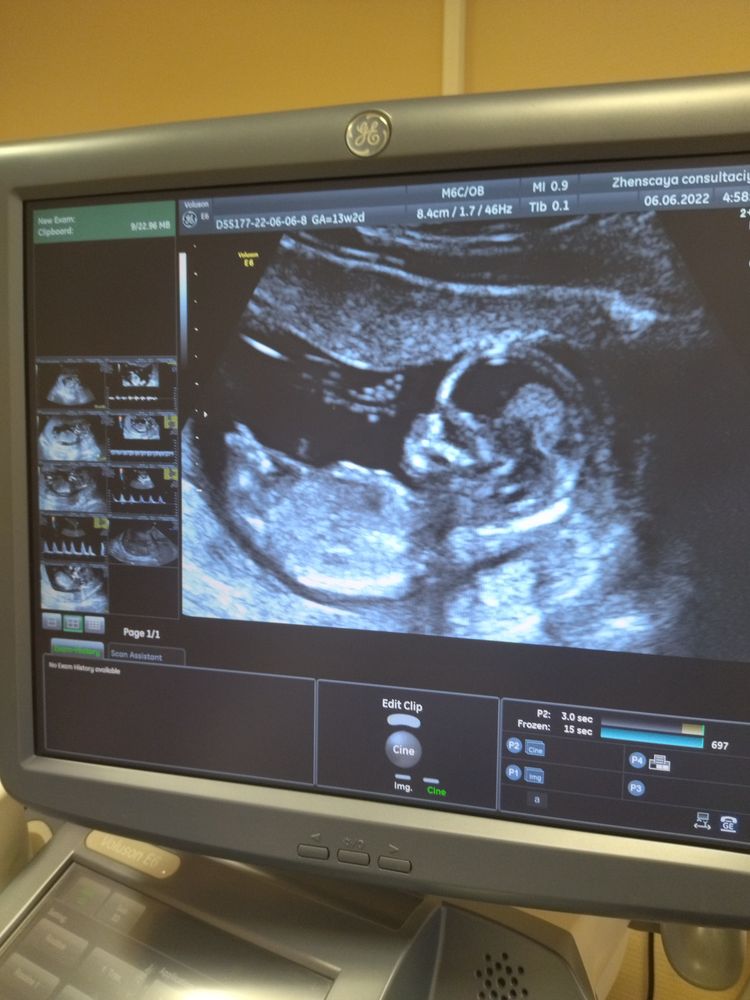

Первый скрининг 13,2

Сходила на первый скрининг, вроде хорошо всё, но пол не предположили) подождём ещё, пусть растёт крепким и здоровеньким бусинка))

06.06.2022